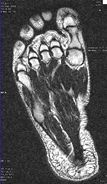

Die nachfolgenden Kernspin-Aufnahmen (MRT) zeigen links den Vorfuß ohne Deformation; die Zehengrundgelenke sind alle sichtbar. Rechts sind dagegen die Zehengrundgelenke nicht mehr in einer Ebene, die Zehen sind zusammengedrückt; der Fuß ist deformiert.

© fair2feet